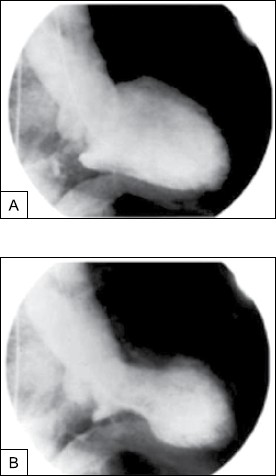

Mulher de 62 anos, previamente saudável, apresenta dor torácica subesternal e dispneia nas últimas 2 horas. O desconforto começou minutos depois de saber que seu filho havia se ferido gravemente em um acidente automobilístico. O histórico é notável para hipertensão arterial. Exame físico: pressão arterial: 152 x 84 mmHg; frequência cardíaca: 88 bpm; saturação de O2: 96%; tórax normal; exame cardíaco: não há galope ou sopro; extremidades sem edema. ECG: inversões difusas da onda T. Exames laboratoriais são inespecíficos e a troponina cardíaca é de 1,07 ng/mL (normal <0,01 ng/mL). O desconforto torácico persiste, apesar da nitroglicerina IV, e a angiografia coronária é realizada. Não são encontradas estenoses coronárias. A ventriculografia esquerda é mostrada a seguir.

(Arquivo pessoal: imagem usada com autorização.)

Nessa circunstância, é correto afirmar: